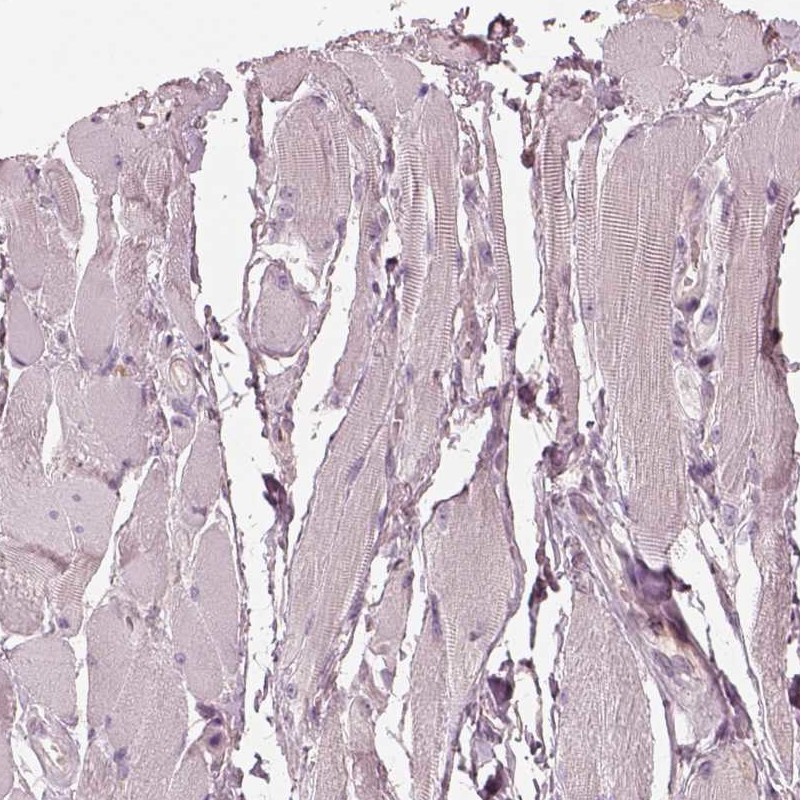

Immunohistochemistry analysis in human small intestine and skeletal muscle tissues using Anti-SDCBP2 antibody. Corresponding SDCBP2 RNA-seq data are presented for the same tissues.